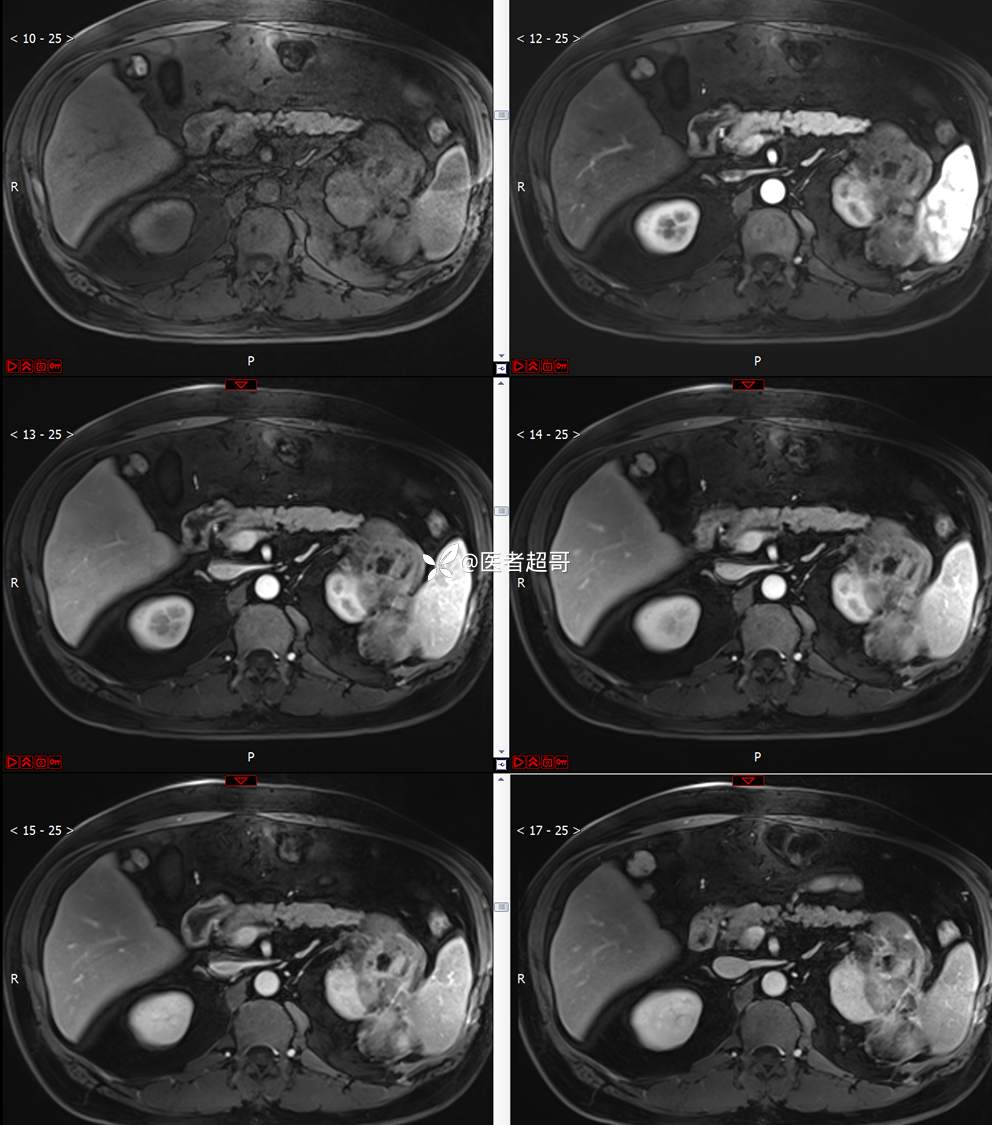

主 诉:查体发现左肾肿物9天。

现病史:患者9天前于附属医院行常规腹部CT检查时,发现左肾占位性病变并肾周脂间隙软组织增多,自述无明显腰腹部不适,无尿频、尿急、尿痛及肉眼血尿,未予特殊治疗,患者近期无头晕头迷,胸闷气急,腹胀腹泻及其他部位明显不适,遂至我院就诊,门诊以“肾肿物”收入院,患者自发病以来,精神可,睡眠饮食可,大便正常,体重无明显减轻。